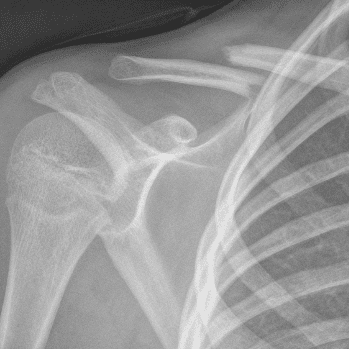

Simuliert den Dienst durch subtile oder schwierige Fälle und einige Normalbefunde.

30 Fälle